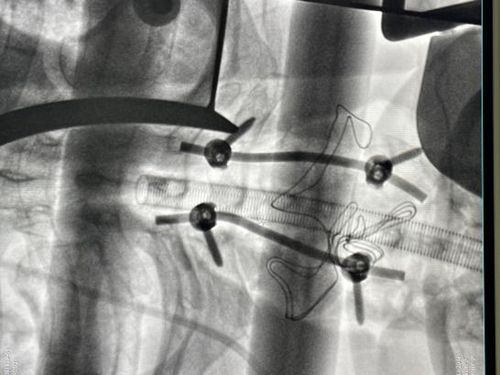

家住济南的于先生因摔伤致右髋部疼痛来院急诊就诊,X线显示右侧股骨颈骨折。经术前评估,专家组决定使用机器人辅助导航置钉进行微创手术。传统的股骨颈骨折微创手术需要手术医生在有限的视野下,凭借对解剖组织的记忆和空间构想,配合术中X光透视来完成手术操作。李连欣主任团队通过机器人导航系统,完成术中实时3D建模,在此基础上完成骨折复位,并通过智能规划进行可视化辅助置钉,手术迅速、微创,股骨颈骨折复位固定良好。

泰安市的程先生头颈部被高空坠物砸伤,经检查为颅骨骨折、脑出血、颈椎C7骨折,C6双侧及C7椎体右侧椎板骨折,脊髓损伤。患者伤情严重,被迅速转往创伤重症病房,行颈椎后路切开复位内固定术。手术顺利完成,目前患者病情稳定,神经功能开始恢复。